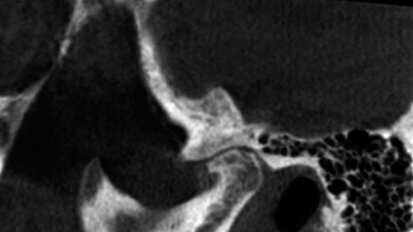

CBCT: ultimi abstracts riportati dalla letteratura

La Cone Beam Computed Tomography (CBCT) sta giocando un ruolo sempre più importante nella diagnosi e nella progettazione del trattamento implantare, ...